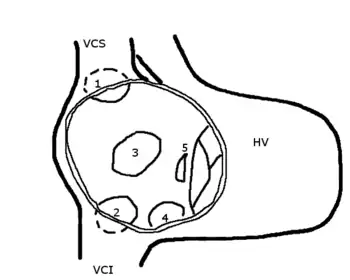

HV: right ventricle; VCS: superior vena cava; VCI: inferior vena cava

1: upper sinus venosus defect; 2: lower sinus venosus defect; 3: secundum defect; 4: defect involving coronary sinus; 5; primum defect.

The six types of atrial septal defects are differentiated from each other by whether they involve other structures of the heart and how they are formed during the developmental process during early fetal development.

A sinus venosus ASD is a type of atrial septum defect in which the defect involves the venous inflow of either the superior vena cava or the inferior vena cava.

A sinus venosus ASD that involves the superior vena cava makes up 2 to 3% of all interatrial communication. It is located at the junction of the superior vena cava and the right atrium. It is frequently associated with anomalous drainage of the right-sided pulmonary veins into the right atrium (instead of the normal drainage of the pulmonary veins into the left atrium).[20]

The interatrial septum can be divided into five septal zones. If the defect involves two or more of the septal zones, then the defect is termed a mixed atrial septal defect.[22]